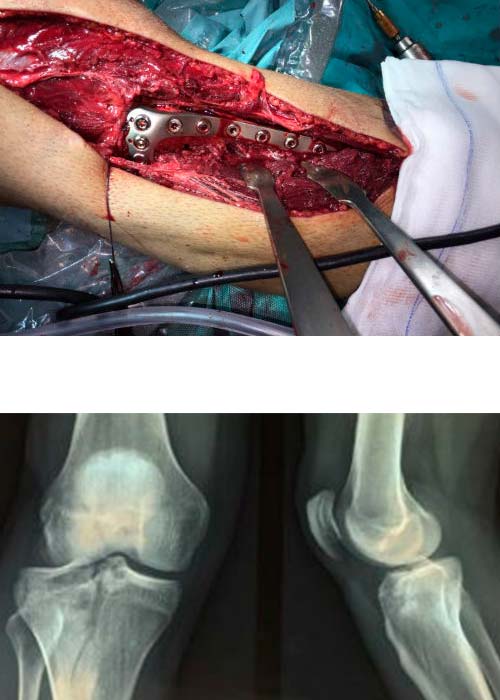

Postoperatorio

Evoluciona satisfactoriamente durante el postoperatorio con control analgésico mediante bomba de perfusión contínua.

Movilización progresiva mediante ortesis de rodilla articulada.